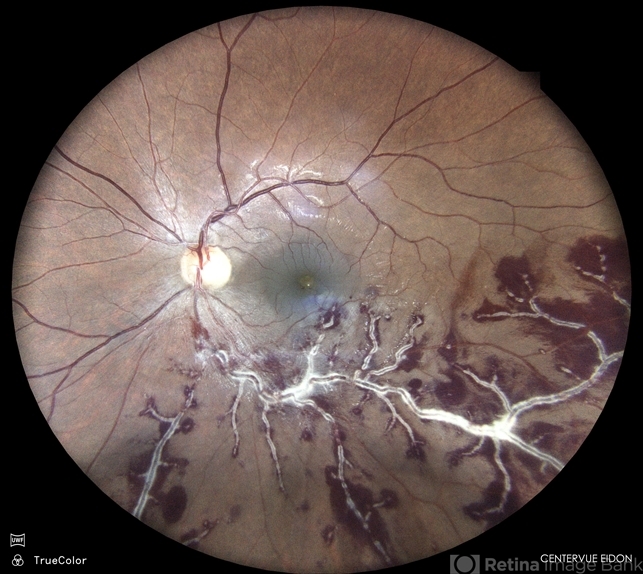

- CMV retinitis

- Colour fundus photograph of a 37 year old male with cytomegalovirus retinitis with macular edema